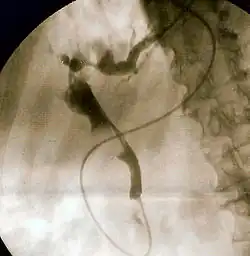

Ретроградная холангиопанкреатография (РХПГ; англ. Endoscopic retrograde cholangiopancreatography, ERCP) — эндоскопический метод исследования жёлчных протоков и протока поджелудочной железы, сочетающий эндоскопию с рентгеноскопическим исследованием. Является одновременно диагностической и лечебной процедурой.

1. Премедикация (седация или общая анестезия) 2. Введение дуоденоскопа через рот, пищевод и желудок в двенадцатиперстную кишку к большому дуоденальному сосочку 3. Катетеризация протоков с введением рентгеноконтрастного вещества 4. Рентгеноскопическая визуализация протоковой системы